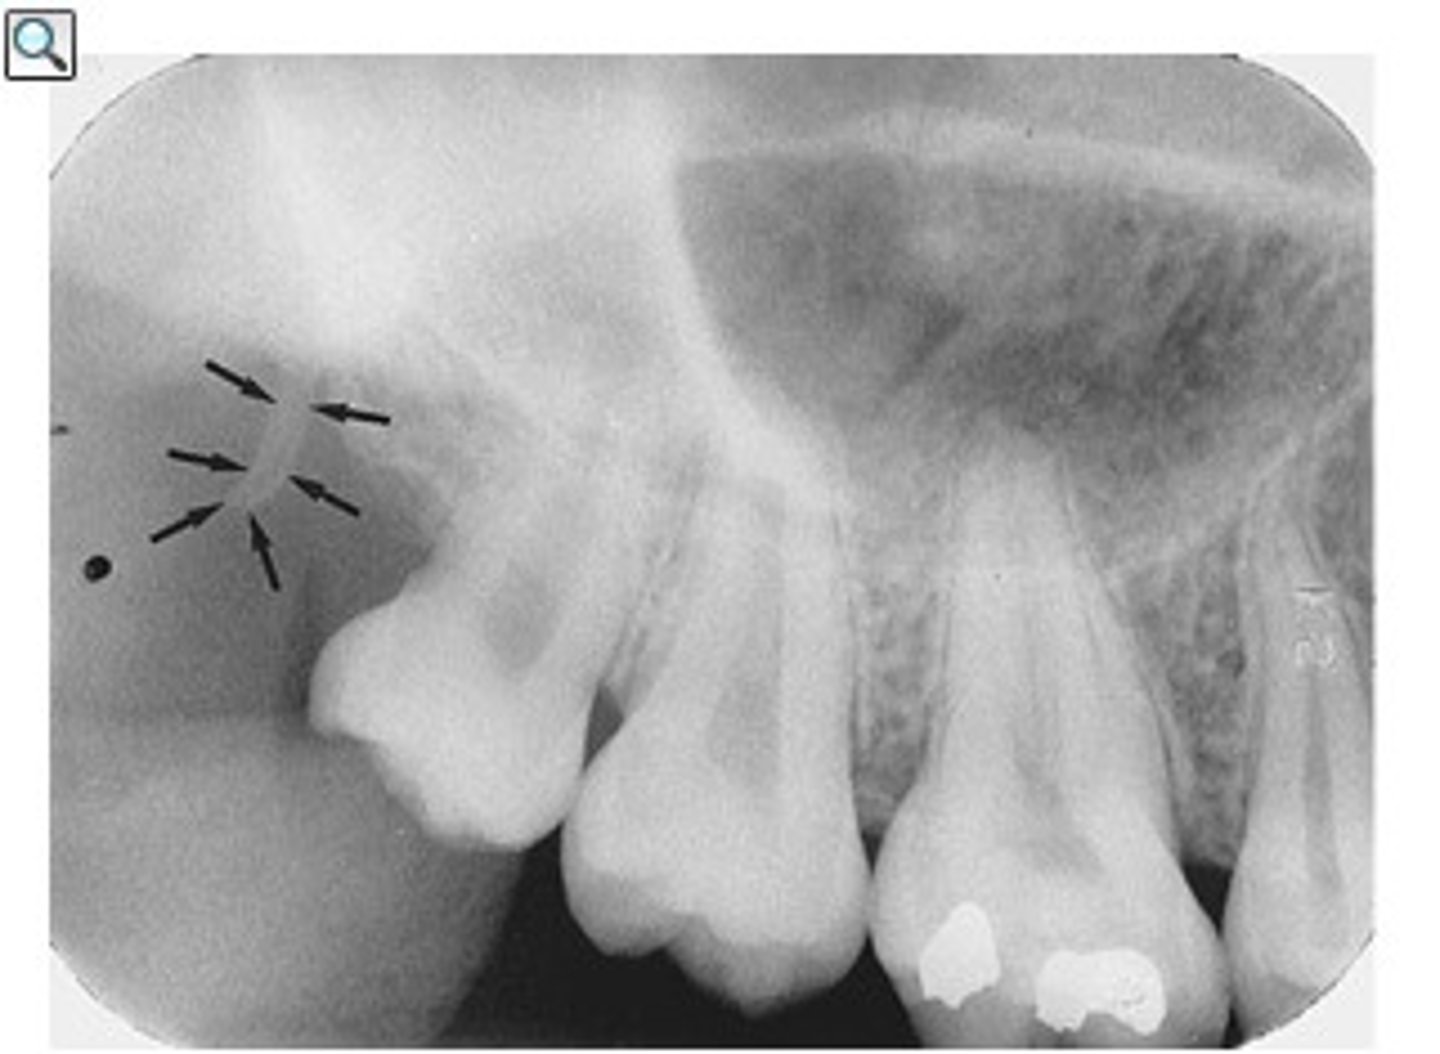

external oblique ridge

dense white line distal to the last molar and moving across root of molars

internal oblique ridge

located below the external oblique ridge

less dense

ridge of bone that extends across roots